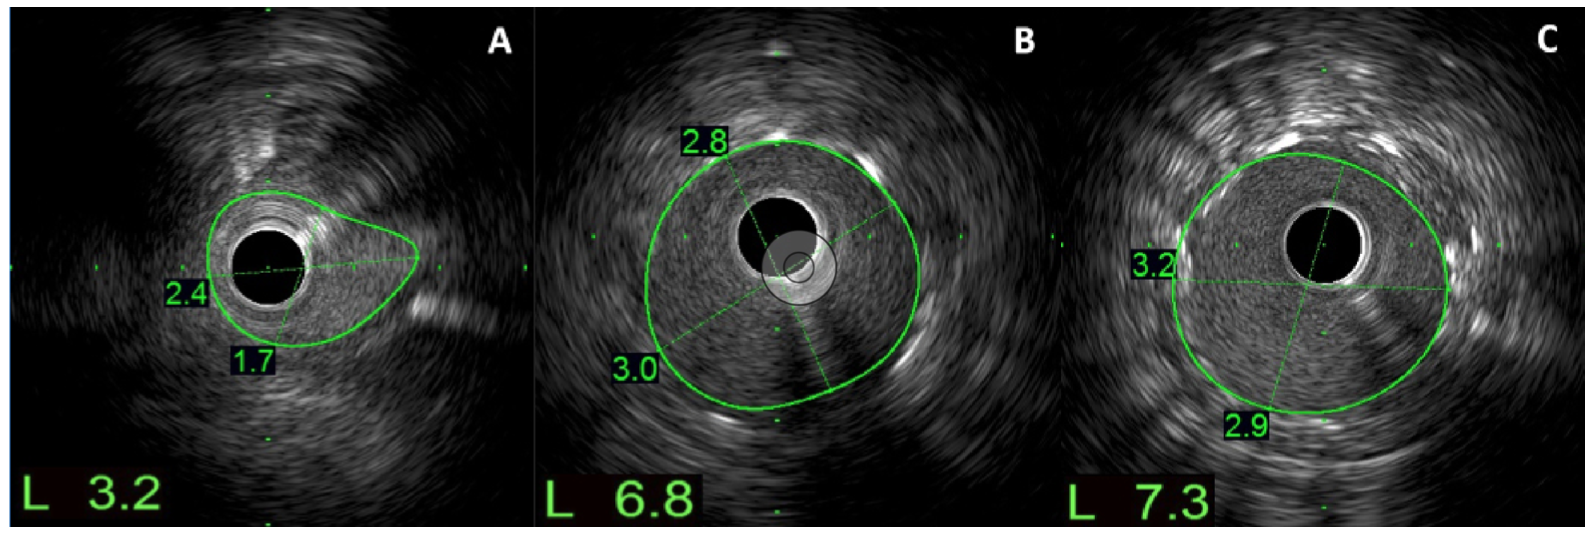

Intravascular ultrasound (IVUS) confirmed wiring of the central lumen, with 4 mm of protrusion into the aorta. The ostial RCA had a minimal lumen area of 3.2 mm2, likely due to mechanical compression at the aorto-ostial junction (Figure 2A; Video Series). A 3.5- x 14-mm drug-eluting stent was deployed and postdilated with a 4.0-mm non-compliant balloon at high pressure. IVUS showed minimal stent area of 6.8 mm2, with stent expansion of 93% (Figures 2B and 2C; Video Series).